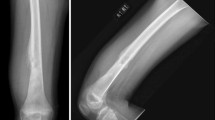

Osteosarcoma (OS) is an osteoid-producing malignancy of mesenchymal origins. This high-grade tumor is the most common primary malignancy of bone and is often fatal in both children and adults. While primary bone cancers represent less than 0.2% of all cancers [1], according to the National Cancer Institute SEER (Surveillance, Epidemiology, and End Results) program, their frequency has been increasing by 0.3% per year over the last decade [2]. While OS occurs most frequently in patients between 5 years of age and early adulthood, incidence peaks again in the older (>65) populations and has been associated with pre-existing Paget’s disease and prior radiation therapy [3,4,5,6,7]. Collectively, the metaphysis of the lower long bones, specifically the distal femur and proximal tibia, are the most commonly involved primary sites, with patients over 25 displaying a greater variety of bony locations [3].

Due to the complex nature of primary bone malignancies, diagnosis of OS is best accomplished via a comprehensive multidisciplinary approach [89]. Often, the first sign of potential bone malignancy is intermittent pain around the affected area with or without a palpable mass [90]. When involving areas around the knee joint, pain exacerbated by weight bearing may manifest as a limp; occasionally, patients will present with a recent bout of bone trauma [91]. As previously mentioned, any older adult with a history of Paget’s disease has an increased risk of developing OS, most notably of the pelvis [92], and this transformation is associated with a poor prognosis [93].

Various serum markers have been investigated for their utility in diagnosing and tracking progression and recurrence. Alkaline phosphatase (ALP) and lactose dehydrogenase (LDH) are useful serum biomarkers, with ALP carrying the most diagnostic value in OS [94, 95]. ALP has also been shown to correlate positively with tumor volume, which carries additional useful prognostic implications [94,95,96]. LDH has also been shown to correlate with tumor volume; however, the correlation is weaker than for ALP and is mainly a result of nonspecific metabolic demand [95]. If disease is suspected, the first step is to gather plain radiographs of the involved bone and adjacent joint. Any abnormal films then warrant further radiological investigation of soft tissue involvement and possible primary lung metastasis via magnetic resonance imaging (MRI) and computed tomography (CT), respectively [97]. Bone scintigraphy (BS) is often used in conjunction with CT to identify metastases and the presence or absence of metastatic disease remains one of the most important predictors of patient outcome [97, 98]. For a more detailed, flow chart-style approach to patient work-up, please refer to the guidelines put forth by the National Comprehensive Cancer Network (NCCN) for bone cancer, Version 2.2017 [99].

Osteosarcoma subtypes include osteoblastic, chondroblastic, fibroblastic, small cell, telangiectatic, high-grade surface, extra-skeletal, and other lower-grade forms including periosteal and parosteal [111]. Based upon their histological appearances, OS subtypes can be grouped into three categories: high-grade, intermediate-grade, and low-grade. Parosteal OS is a low-grade subtype that is fibroblastic in appearance and limited to the bone surface; however, with time, it may progress to involve deeper structures. For this and other low-grade subtypes, treatment involves surgery alone and carries a favorable prognosis. Periosteal OS is chondroblastic on histology and is the only subtype that falls into the intermediate-grade category. Depending on extent of invasion, treatment for intermediate-grade OS often includes systemic chemotherapy. High-grade OS, which includes the classic osteoblastic subtype, is the fastest-growing and most aggressive group. The majority of OS subtypes fall under this category and include osteoblastic, chondroblastic, fibroblastic, small cell, telangiectatic, high-grade surface, and extra-skeletal. Telangiectatic OS is notable for its profuse vascularity and scant osteoid production, which often complicates tissue biopsy and radiographic identification, respectively [112]. Telangiectatic OS also carries with it an anatomical predilection to the epiphyseal region of the bone. All high-grade OS should be considered micrometastatic at diagnosis and treated with surgery and systemic chemotherapy.